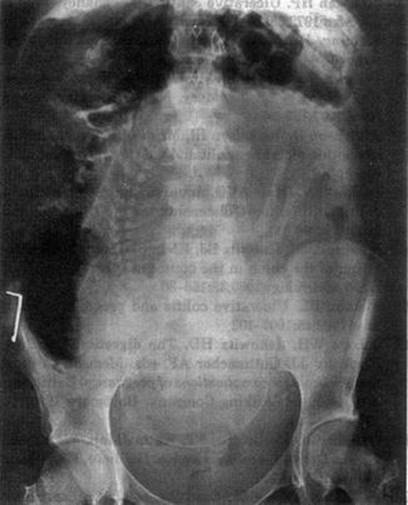

It is difficult to measure colonic dilation in different colonic segments if toxic megacolon is suspected, again, especially in the third trimester (Fig. 8.2).

Fig. 8.2

Toxic dilatation of the colon in 33rd week of pregnancy [129]